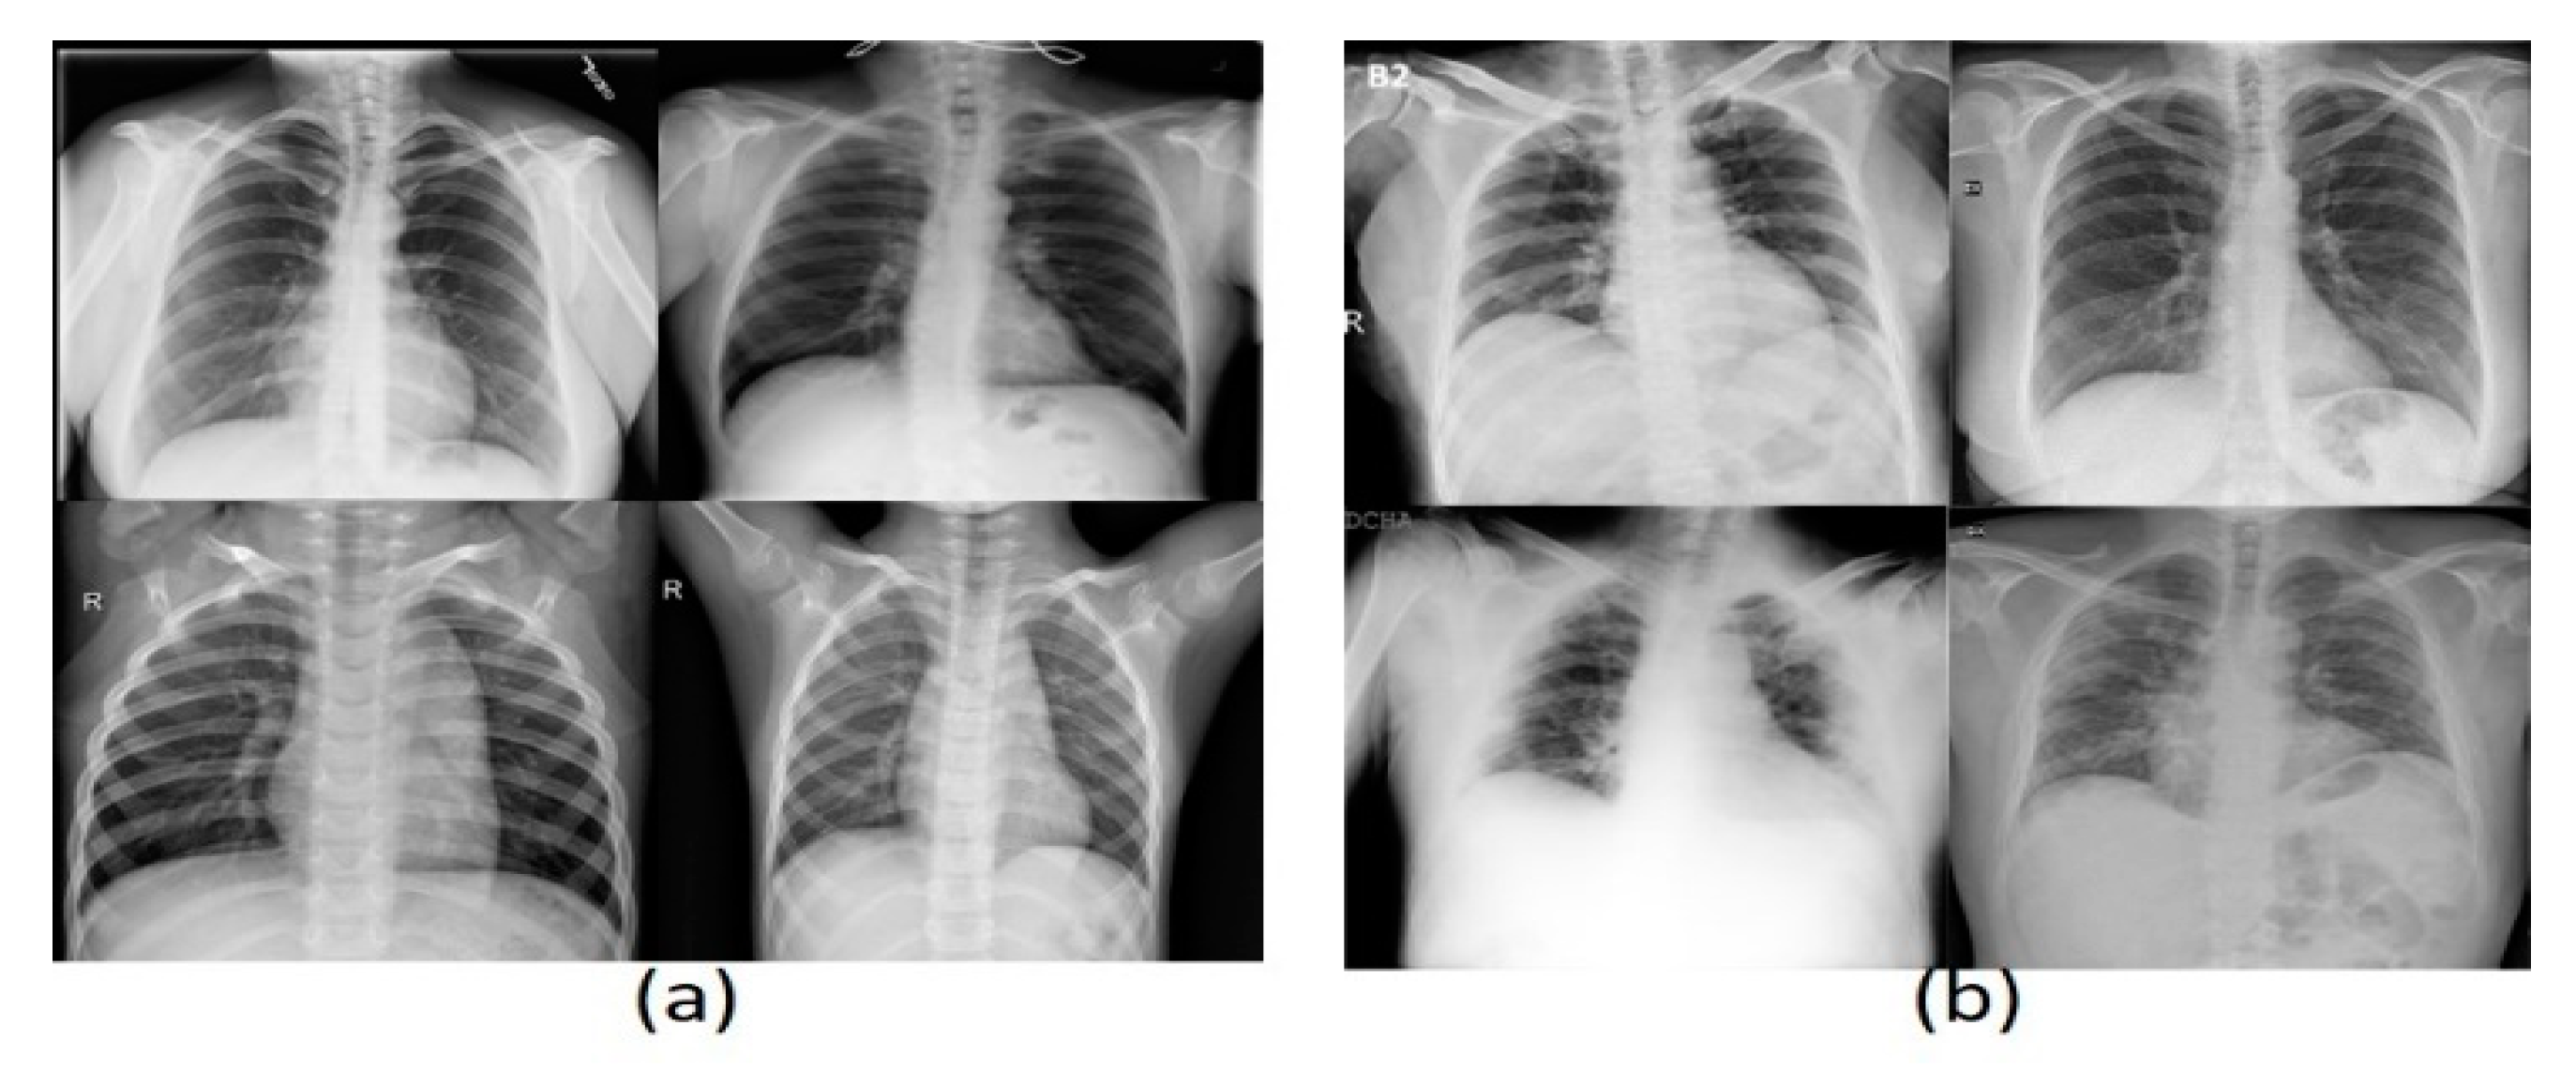

Three datasets were used in these experiments, two of which have images of CXR type, and the last has CT images. The acquired dataset of CT scans was divided into 4001 COVID-19 and 15,684 non-COVID-19 images, whereas the first CXR dataset consists of 219 COVID-19 and 2686 non-COVID-19 images. The second CXR dataset comprises 3616 COVID-19 and 17,549 non-COVID-19 images. The evaluation supports the holdout procedure using 80% training set and 20% testing set. See Table 2 for a brief description of dataset details. Figure 6 and Figure 7 show a montage preview of the CT and CXR images.

Figure 7. Sample of CXR dataset collection: (a) normal cases (b) COVID-19 cases.